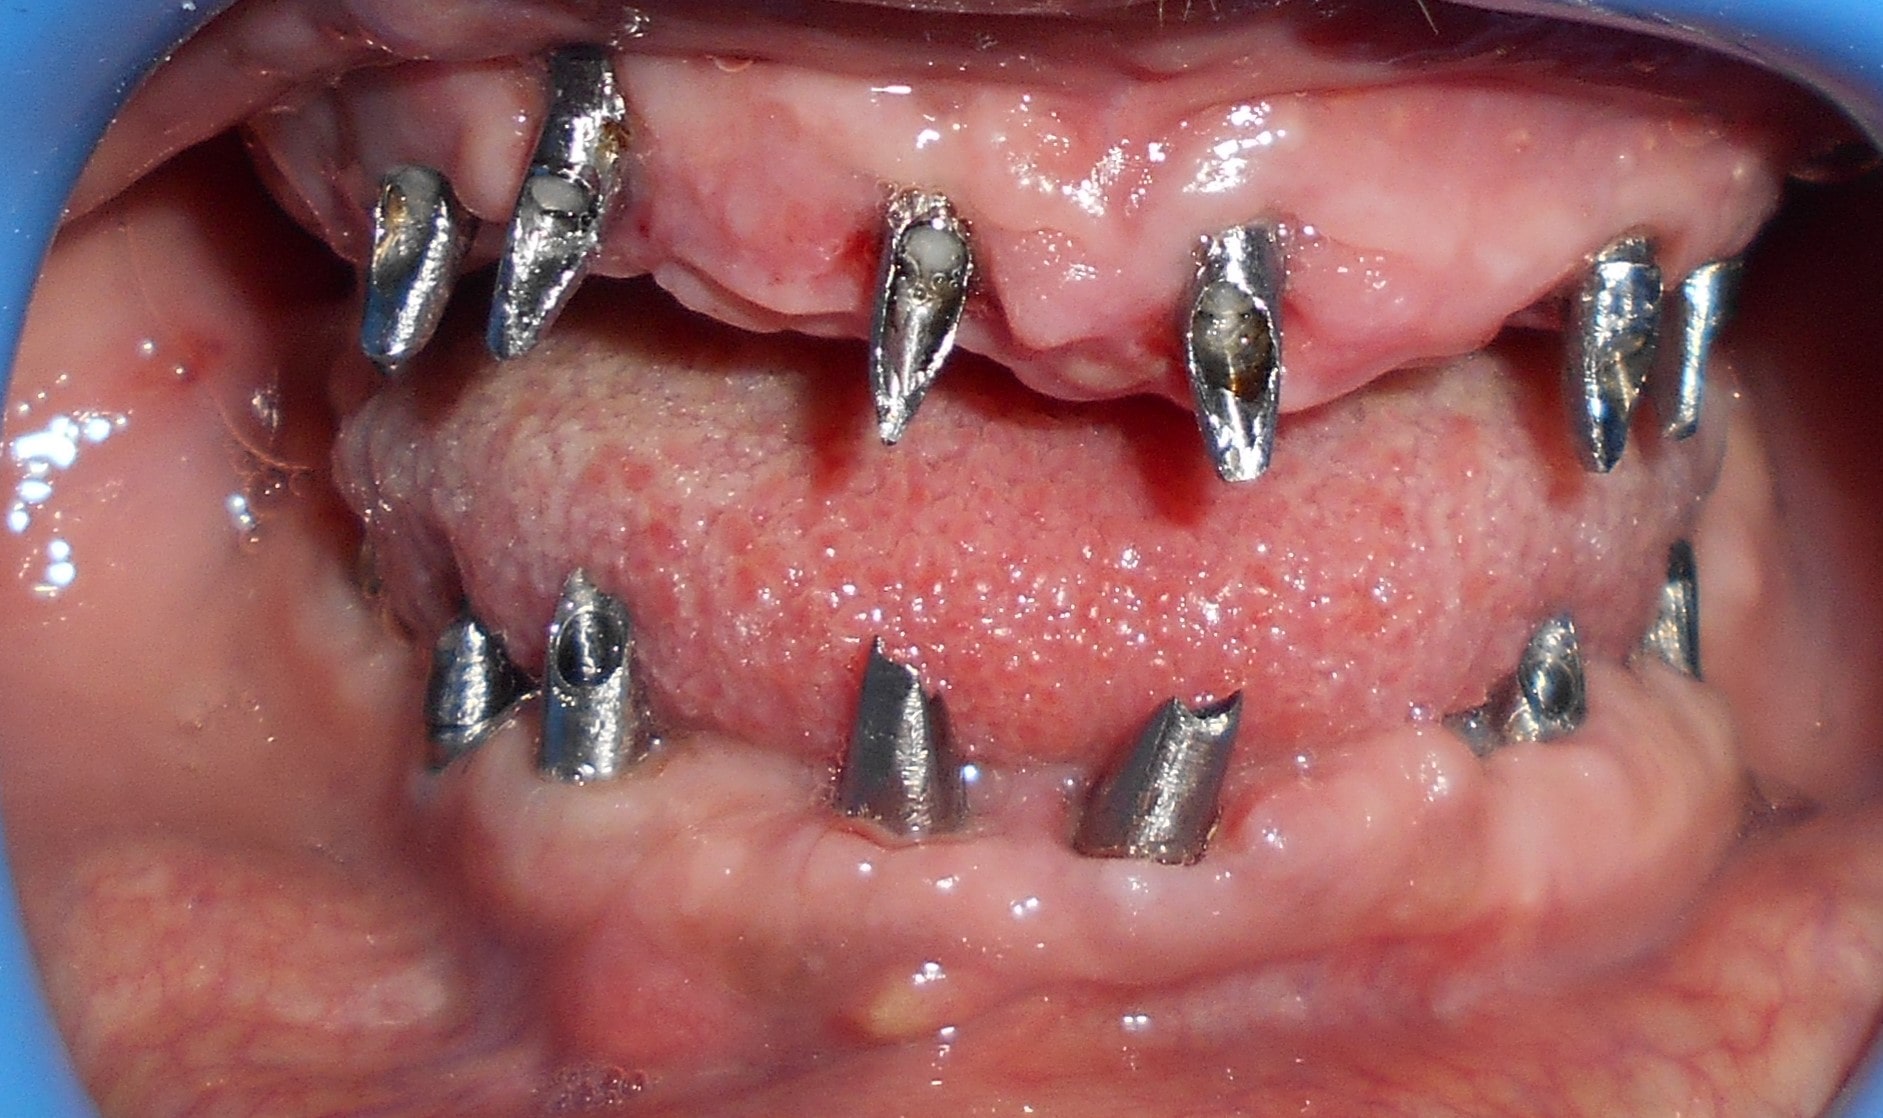

Pacijent 3

Pacijent dolazi sa starim mostovima i izraženom parodontopatijom u donjoj vilici. Urađeno je skidanje postojećih mostova i istovremena ekstrakcija svih parodontopatičhin zuba uz ugradnju sedam implantata u gornjoj vilici i pet implantata u donjoj vilici. Pacijent je nakon tri dana bio privremneo protetski zbrinut sa fiksnim privremeni krunicama koje su fiksirane na tek ugrađenim implantaima. Nakon četiri meseca je izrađen fiksni cirkonijum kermički- bezmetalni most u gornjoj i donjoj vilici. Rad uspešno završen pre tri godine.